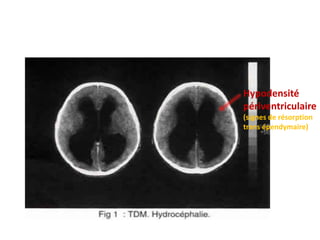

TDM:

Dilatation ventriculaire associée ou non à une

hypodensité périventriculaire.

Hypodensité

périventriculaire

(signes de résorption

trans épendymaire)

TDM: Dilatation ventriculaire associéeou non à une hypodensité périventriculaire. Des orientations étiologiques: tétraventriculaire : arachnoïdite d’origine infectieuse ou post hémorragie méningée tri ventriculaire : sténose, tumeur de l’acqueduc du mésencéphale, anévrisme de l’ampoule de Galien uni ou biventriculaire : kyste colloïde, tumeur thalamique